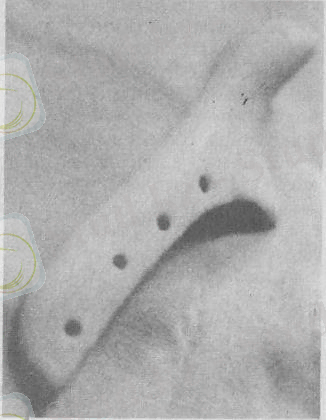

Осы мақсатпен металл және пластмасса қалпақтар (А. Э. Рау-эр, Н. М. Михельсон), тері май қиындысы (Косых С. Ф), диэпителизацияланған Филатов сабағын сүйектің арасына салу (Аимберг А. А. ) суйек жарасын химиялық заттармен түтіндеген азот қышқылымен өңдеп (1-2 минут қоңырланғанша) қосқышқылды сода ерітіндісімен бейтараптау (Великанов М. М. ) . Бүл операция-лардың негізгі әдісі сүйектің көлбеу операциясы (Львов П. П., Рауэр А. Э. ) (50 а, б-сурет) . А. Э. Рауэр буынға құлақ түйінінің қасынан кесуді ұсынады.

50- сурет. Төменгі жақ сүйегінің анкилозына жататын А. Э. Рауэр бойынша остеотомия операциясы